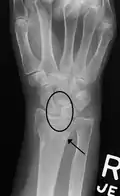

X-ray images indicate scapholunate ligament instability when the scapholunate distance is more than 3 mm, which is called scapholunate dissociation.[7] A static scapholunate instability is generally readily visible, but a dynamic scapholunate instability can only be seen radiographically in certain wrist positions or under certain loading conditions, such as when clenching the wrist, or loading the wrist in ulnar deviation.[6]

Dynamic instability: Increased scapholunate distance (between yellow lines) upon ulnar deviation of the wrist, but not otherwise. -